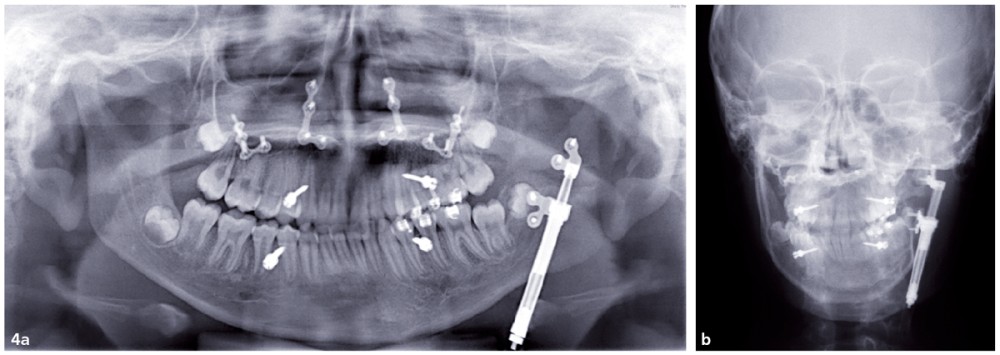

Les examens de contrôle montrent la position du distracteur et la quantité de tissus néoformés (fig. 4a et b).